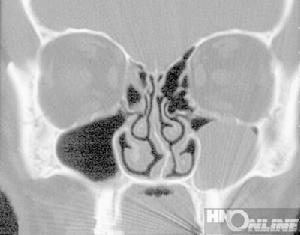

3、鼻竇囊腫患者X線攝片見粘液囊腫鼻竇腔擴大,竇壁變薄或消失、囊腫陰影邊緣光滑、密度均勻。黏膜囊腫在上頜竇內有局限性邊界清晰的半圓形陰影。牙源性囊腫竇內含有牙齒或牙根骨質吸收和囊影。